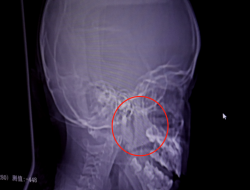

患 者: 小雨 13岁 登封人 术前症状: 左耳听力突然下降 耳内有异物感 发病时间: 11天左右 治 疗 史: 发病后,在镇医院输液治疗10多天,未见 发......